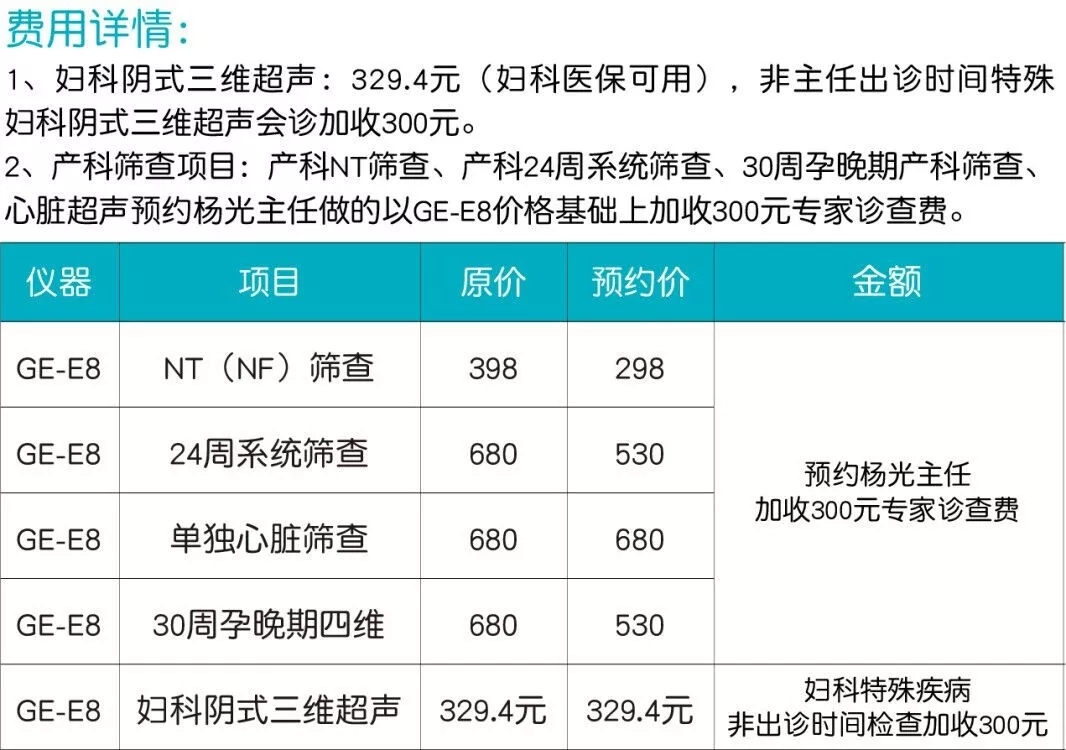

周一至周五上午

杨光主任亲诊

作为大连地区高知名度的超声科医生,杨光不仅在胎儿超声诊断领域有着丰富的临床经验,同时还精通妇产科常见疾病及疑难杂症的超声诊断。杨光主任强调,妇科阴式三维超声对于女性疾病的检查是较为重要,能够较早的发现女性的疾病,对比传统B超拥有着更多的优势。

目前,杨光主任每周一、周三上午出诊妇科阴式三维超声(仅限30人),周五上午出诊产前四维彩超(仅限8人)。周二、周四上午各超声诊室带教指导和疑难超声会诊。由于杨光主任预约客户较多,有需求的女性抓紧预约!